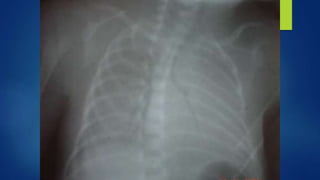

Hallazgos radiográficos

A. Hallazgos radiográficos, en infantes con SAM

incluyen:

 Infiltrados difusos.

 Consolidación

 Atelectasia

 Derrame pleural

 Espacios aéreos (neumotórax, neumomediastino)

 Pulmón húmedo, similar a lo hallazgos vistos en la T.T. RN.

 Hipovascularidad

 Aparentemente limpio, apariencia virtualmente normal.